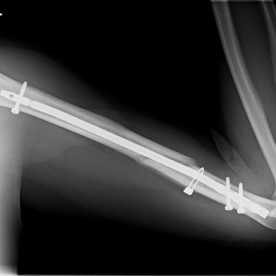

Röntgenbilder